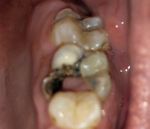

Отломилась часть зуба до десны: удалять или восстанавливать?

Чаще всего ломаются запломбированные зубы, из которых удалена пульпа (см. также: что делать, если при беременности ломаются зубы?). Единицы, полностью лишенные питания, становятся очень хрупкими, что приводит к появлению сколов даже при незначительной нагрузке. Однако если эта неприятность произошла, не стоит спешить удалять зуб.

В случаях, если зуб сломался ниже уровня десны и от него остались только корни, или он настолько поврежден, что на его месте виднеется одна стенка, грамотно проведенная процедура реставрации позволит единице прослужить еще не один год (рекомендуем прочитать: что делать, если сломался зуб, а его корень остался в десне?). Естественная для организма ткань всегда лучше, чем имплантат или мост.

В вышеописанных случаях врачи прибегают к протезированию или наращиванию, поскольку восстановить такой зуб обычной пломбой невозможно. Пациент не должен медлить с походом в стоматологию – врач закроет образовавшуюся полость пломбировочным материалом, чтобы уберечь остатки зуба от разрушения под воздействием бактерий до начала основного лечения.

Показания к удалению

Перед тем как решить, что делать со сломанным зубом, врач проводит диагностику. Он беседует с пациентом, проверяет состояние поврежденной единицы, отправляет человека на рентген, чтобы выяснить, нет ли новообразований или переломов на корнях (подробнее в статье: перелом корня зуба: симптомы, причины и лечение). Врачи стараются всеми способами сохранить зуб, но в некоторых случаях он подлежит удалению:

Если зуб относительно функционален, но на его корне присутствует киста или гранулема, доктор может выполнить ампутацию корня или резекцию его верхушки – единицу получится сохранить и отреставрировать. В случае сильного воспалительного процесса с развитием периостита, абсцесса или образованием большой кисты элемент зубного ряда придется удалить.